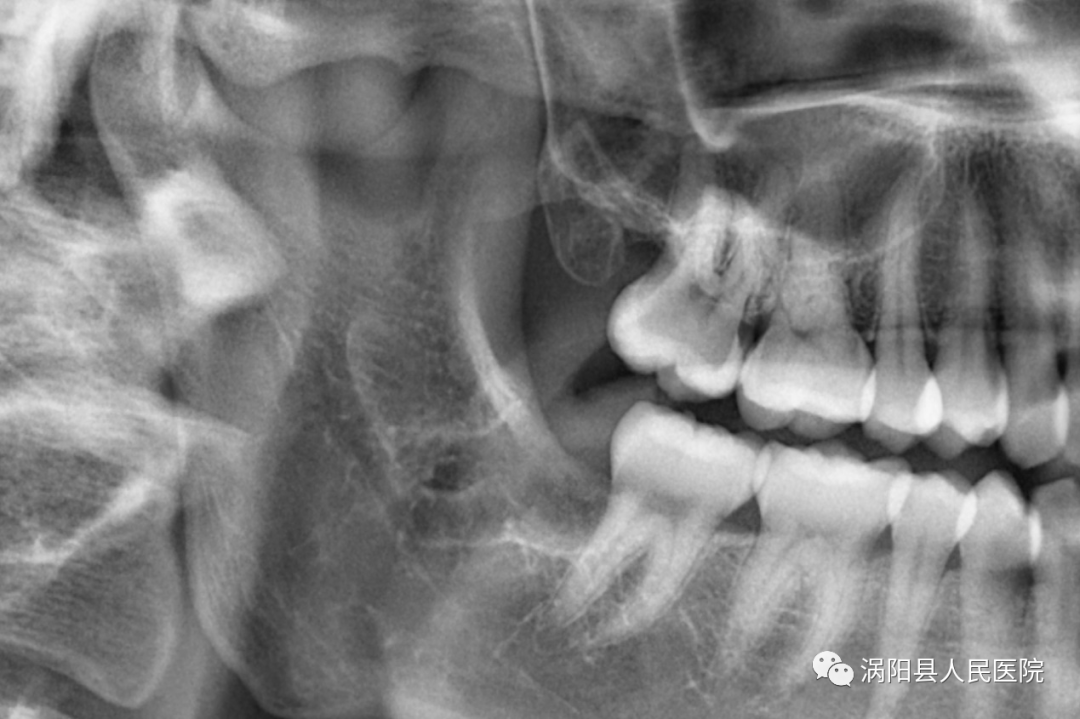

拔除后复查牙片可见周围骨质损伤较小,上颌结节完好。